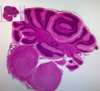

MÓŻDŻEK (H+E):

− Kora – istota szara = ciała komórek (brak otoczki mielinowej),

− Rdzeń – istota biała = zmielinizowane włókna (wypustki kom.

nerwowych – aksony i dendryty),

− Opona miękka na zewnątrz,

− 3 warstwy kory:

− warstwa drobinowa,

− warstwa zwojowa (duże komórki Purkinjego),

− warstwa ziarnista,

MÓŻDŻEK (Met. Osmowa):

− Kora – istota szara,

− Rdzeń – istota biała,

− Opona miękka na zewnątrz,

− 3 warstwy kory:

− warstwa drobinowa,

− warstwa zwojowa (duże komórki Purkinjego),

− warstwa ziarnista,

− Metoda osmowa wybarwia lipidy na czarno = istota biała która jest wewnątrz barwi się na

czarno przez obecność osłonki mielinowej, która jest błoną komórkową oligodendrocytu i

zbudowana jest z fosfolipidów,

O preparacie:

- opona miękka

- istota szara: warstwa splotowata, zwojowa, ziarnista - istota biała

Móżdżek ssaka